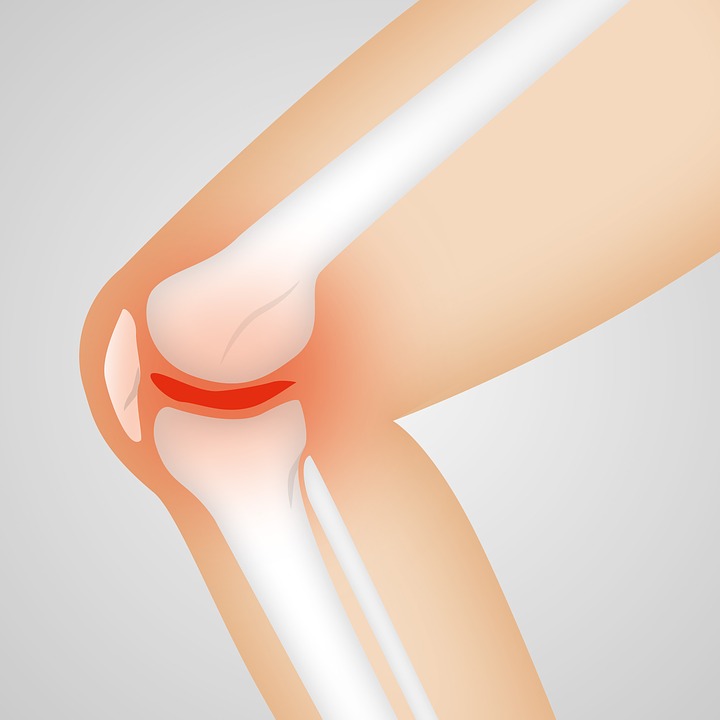

A artrose, também conhecida como osteoartrite ou osteartrose, é uma doença que se caracteriza pelo desgaste das articulações. É importante entender que o local onde os ossos se encontram é coberto por cartilagem (material borrachoso e lubrificado), que favorece que os ossos deslizem um sobre o outro, provocando o mínimo de atrito. O desgaste desta cartilagem provoca o aumento da fricção entre os ossos e leva à inflamação local (artrite), gerando dor e incapacidade funcional. Segundo dados do Ministério da Saúde de 2016, um em cada 13 brasileiros tem o problema.

Os principais sintomas da artrose são: dor na região (quadril, joelho, ombro, por exemplo), rigidez muscular, estalidos na articulação, dificuldade para realizar atividades diárias simples como ficar em pé por muito tempo, sentar-se em cadeiras ou sofás baixos, caminhar, sair de carros, cruzar as pernas, deformidade articular, e sentir dor mesmo estando parado.

O diagnóstico da artrose é realizado por meio de avaliação clínica e exames de imagem, como raio X e ressonância magnética, para verificar a amplitude da doença. Os casos de artrose moderados são tratados com medicamentos, mas, segundo o ortopedista, provavelmente esse paciente irá passar por um procedimento cirúrgico para a implantação de uma prótese. “Se dá para o paciente ter uma qualidade de vida razoável com o tratamento clínico, esta é a primeira opção. É fundamental o controle do peso, pois a obesidade agrava os casos de artrose no joelho. A cirurgia para a indicação de uma prótese é indicada nos casos em que o paciente já não está tendo uma boa qualidade de vida”, salienta o cirurgião Herculano Braga Filho.

Recentemente, o Instituto de Ortopedia da Universidade de São Paulo (USP) vem testando uma nova técnica para tratar a artrose de joelho. A subcondroplastia, uma técnica que reconstrói o osso que está abaixo da cartilagem do joelho, é indicada apenas para artroses leves e medianas.

A técnica, criada nos Estados Unidos, está sendo aplicada em pacientes do Instituto de Ortopedia e Traumatologia do Hospital das Clínicas (HC) que sofrem com artrose moderada. O procedimento é minimamente invasivo e reconstrói o osso subcondral (que fica abaixo da cartilagem) quando há perda do volume da cartilagem que envolve toda a estrutura do joelho. O procedimento consiste no preenchimento das áreas lesionadas com material sintético pastoso à base de fosfato de cálcio. A técnica, que vem sendo aplicada por meio de protocolo de pesquisa no HC da Faculdade de Medicina da USP em 30 pacientes entre 40 e 75 anos, tem se destacado na área médica de ortopedia por seus resultados surpreendentes.